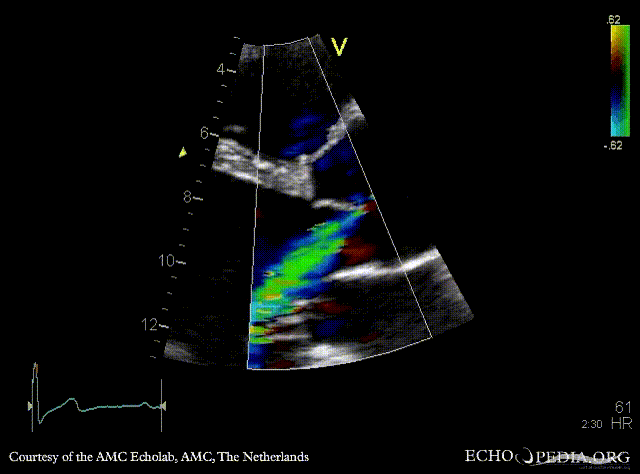

E00555.gif

PSAX with Color Doppler: moderate aortic regurgitation Suprasternal view